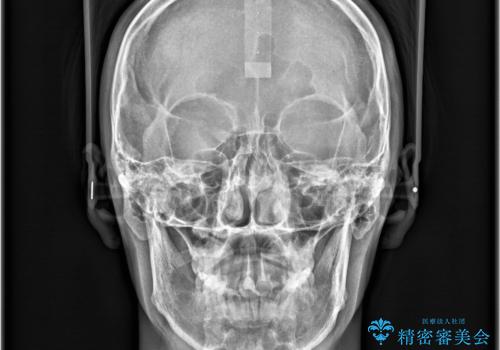

- 「歯のでこぼこを治したい 1年くらいで矯正を終わらせたい」を主訴に来院された患者様です。

叢生量は多く無く歯の傾斜も標準傾斜だったので歯は抜かずにワイヤー矯正で治療を行いました。

左側は2級傾向が強く臼歯の遠心移動をご提案しましたが、1年以内に矯正を終わらせたいという患者様のご意向で希望されず叢生を改善する矯正となりました。